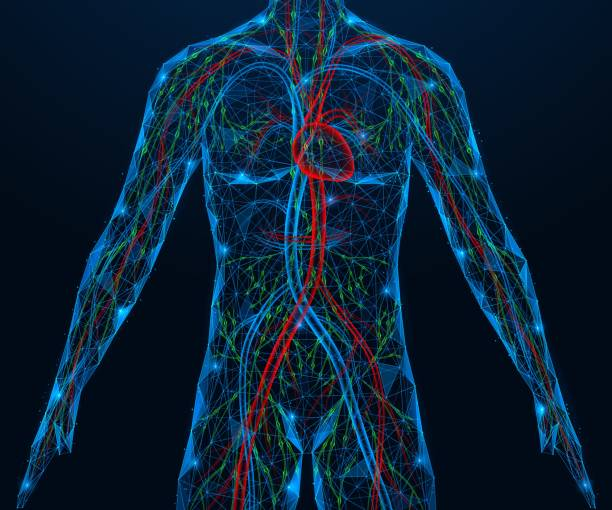

De studie richtte zich op het vaatstelsel, dat zuurstof en voedingsstoffen door je lichaam vervoert en essentieel is voor energieniveau, concentratie en herstelvermogen.

Tijdens de test werden drie soorten producten gebruikt: een vape met nicotine, een nicotinevrije vape en een traditionele sigaret. Er is gekeken naar de snelheid van de bloedstroom, de zuurstofniveaus in het bloed en de aanpassing van de bloedvaten aan veranderende zuurstofniveaus.

Bij alle vormen van dampen werd een verandering in het lichaam waargenomen. Zelfs zonder nicotine in de vape, daalde de bloedstroom en nam de zuurstofniveaus af, waardoor het lichaam harder moet werken om goed te functioneren, zelfs zonder verslavende stoffen.

Bij gebruik van zowel nicotinehoudende als nicotinevrije vapes, wordt de hoeveelheid zuurstof in het bloed tijdelijk verminderd. Dit heeft directe invloed op het energieniveau en uithoudingsvermogen, vooral in de grote slagaders die zuurstofrijk bloed naar belangrijke spiergroepen transporteren.

Een goed zuurstoftransport is essentieel voor denken, bewegen, herstellen, en ontspannen. Verminderde efficiëntie kan leiden tot vermoeidheid en gebrek aan focus, en op lange termijn invloed hebben op je fitheid.

Uit het onderzoek bleek dat het lichaam al direct reageert op vapen. De bloedvaten werden iets stijver en de zuurstofvoorziening daalde tijdelijk, wat aangeeft hoe gevoelig het lichaam is voor ingeademde stoffen.